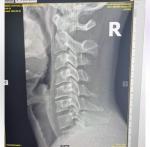

Здравствуйте. На rg-граме шоп двух проекциях костно-деструктивных изменений не определяется. Физиологический лордоз сглажен. Уплотнение замыкательных пластин тел позвонков, контуры их чёткие, ровные. Остеофиты по передним углам тел позвонков в блоке с4-с6, высота мпд снижена. Заострение крючковидных возвышений. Формирование патологического кифоза в блоке c4-c6. Заключение: РГ признаки распространённого остеохондроза первой степени. Ограниченный дефспондилёз первой степени в блоке c4-c6. унковертебральный артроз.